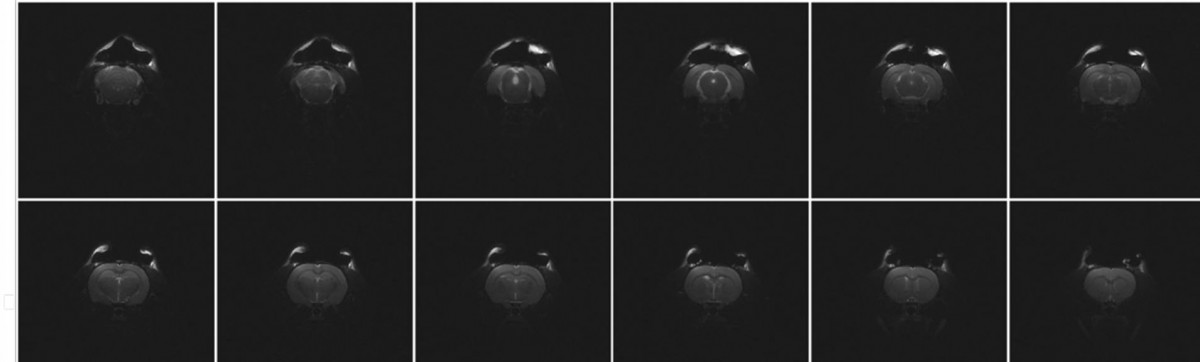

Optogenetic functional Magnetic Resonance Imaging (ofMRI) is a technique that combines optical activation of the brain with functional MRI. This allows to monitor cell type-specific mapping of functional neural circuits and their dynamics across the whole brain.

The stimulation is achieved through an optical fiber that delivers light of a specific wavelength deep into the brain. This in turn sets the demand for coils that give access for these fibers while still maintaining best possible SNR and brain coverage.

RAPID Biomedical meets this requirement with a set of different coils starting with single channel implantable loops that are connected to a separable coil electronics only for the fMRI. The obvious benefit of these coils are the maximized access to the skull. For better coverage and SNR in deeper brain regions we added quadrature coils as well as 3 channel phased arrays with different openings.

F. Albers, L. Wachsmuth, T.M.van Alst, C. Faber: Multimodal Functional Neuroimaging by Simultaneous BOLD fMRI and Fiber-Optic Calcium Recordings and Optogenetic Control.

Molecular Imaging and Biology, ISSN 1536-1632, DOI 10.1007/s11307-017-1130-6 (2017)

with RAPID Biomedical 3-channel rat head array P-H03LE-094-01543